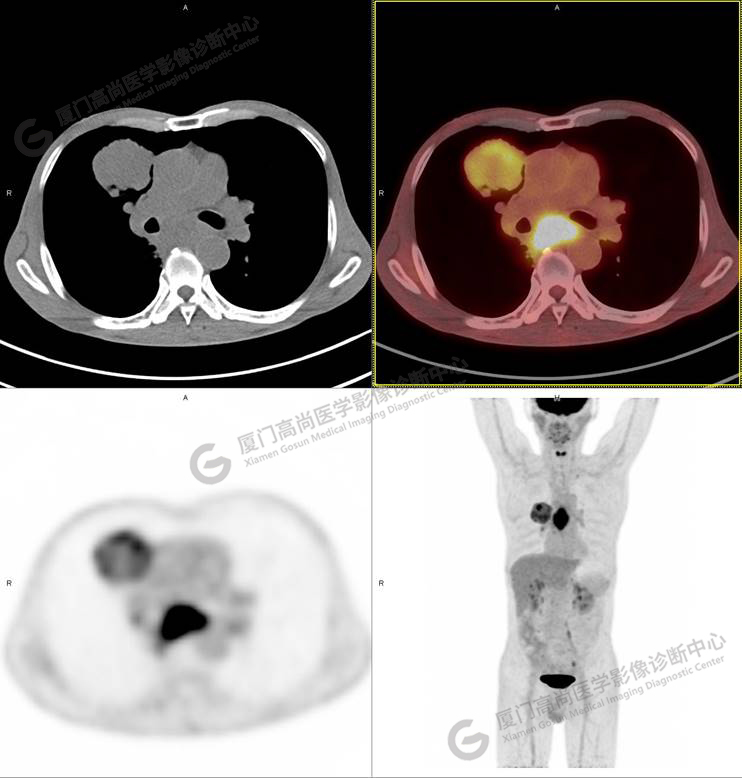

同時(shí)發(fā)現(xiàn)食管中段管壁增厚,管腔狹窄,放射性攝取不均勻性增高,SUVmax 9.67。

矢狀位清晰顯示,食道病灶累及長度約6cm